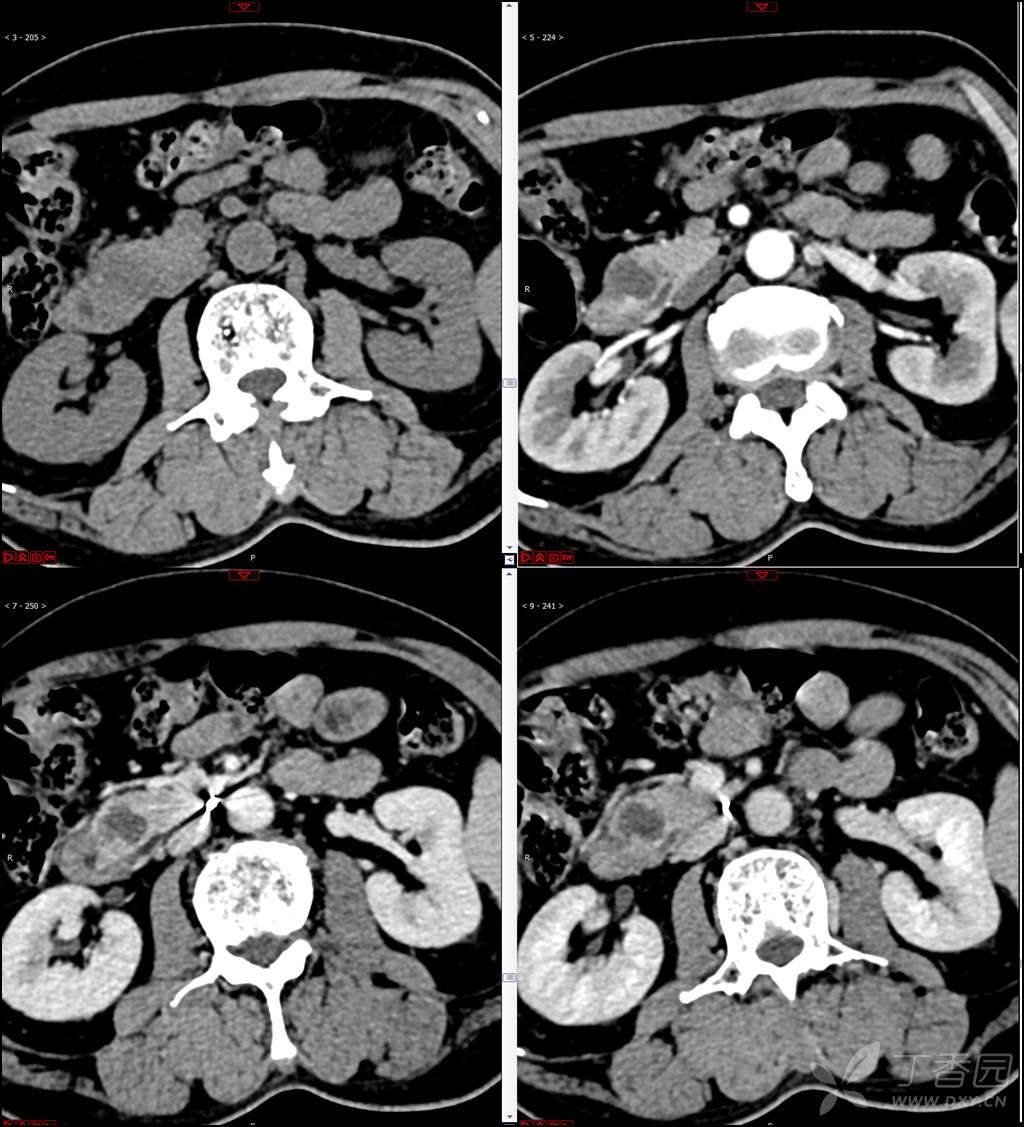

【影诊笔记521】老年男性,黑便就诊,请分析~『回帖即可查阅答案』

患者年龄:67岁

主诉:黑便1周。

现病史:患者1周前无明显诱因出现黑便伴头晕、心慌,无胸闷、胸痛,后仍间断黑便,2022-10-27就诊于某市中医院,行胃镜检查示:十二指肠溃疡伴出血,给予止血、抑酸等对症治疗,效果欠佳。今为行进一步治疗就诊于我院急诊,门诊完善新型冠状病毒核酸检测后以“十二指肠溃疡伴出血”收入我科。患者自发病以来,神志清,精神可,未进食,睡眠可,小便未见异常,黑便,近期体重无明显增减。